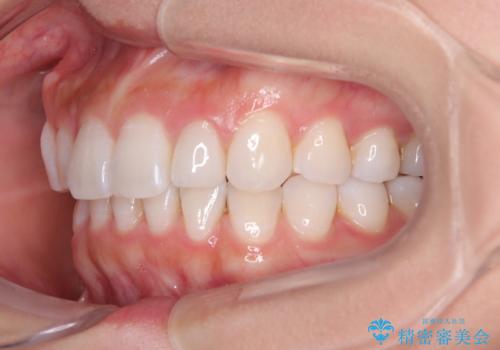

【モニター】前歯のデコボコと小さい前歯 インビザライン矯正とオールセラミッククラウン補綴治療

- 前歯の歯並びと生えてきたときから小さい前歯を気にして来院された患者様です。

上下前歯の歯列不正はインビザラインにより整え、その後に、矮小歯の前歯をオーダーメイドタイプのオールセラミッククラウンにて補綴治療することとしました。

セラミッククラウンにて大きさを変更することを前提に矯正治療を開始したため、大変満足のいく仕上がりとなりました。